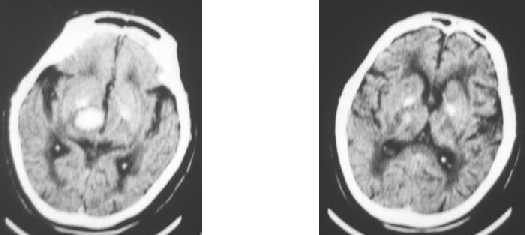

Nontraumatic ICH : midbrain - pons